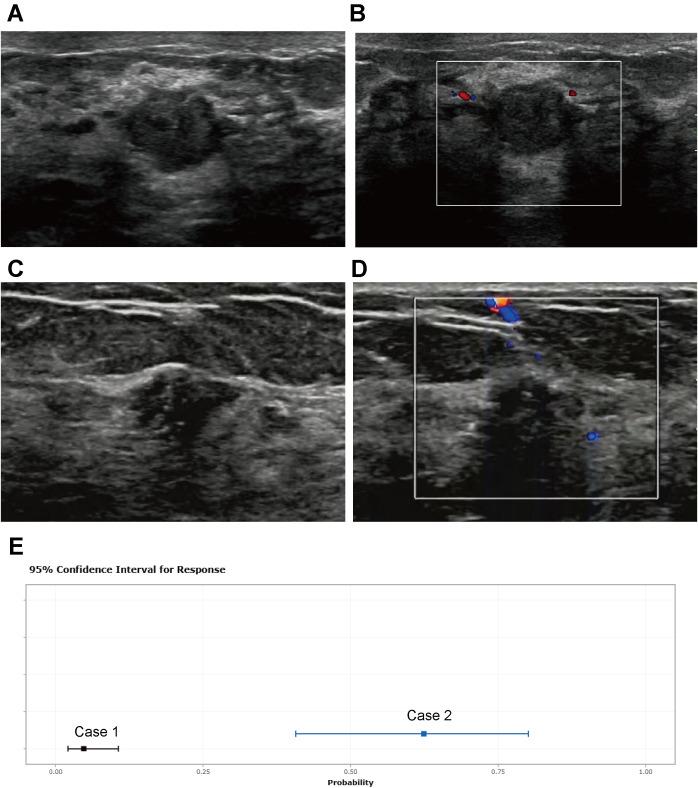

Intraductal Papilloma (IDP) and Ductal Carcinoma (DCIS) are significant benign and pre-invasive breast lesions, respectively. This study aimed to investigate ultrasound features and develop a predictive nomogram for discriminating between IDP and DCIS.

Conducted at Quanzhou First Hospital over a three-year period, 389 patients were enrolled with detailed ultrasound examinations and confirmed pathological diagnoses. IDP was classified into Grades 3, 4, and 5, whereas DCIS presented with a mass-like morphology. Patients meeting the inclusion criteria underwent rigorous analysis, with exclusion criteria eliminating those with incomplete imaging data or confounding comorbidities. Ultrasound characteristics, including lesion size, shape, margin, and echogenicity, etc., were systematically evaluated and compared between the two groups. Univariate and multivariate logistic regression analyses were conducted to identify significant risk factors. Subsequently, based on these characteristics, both static and dynamic nomograms were developed. The performance of the nomograms was evaluated using the area under the receiver operating characteristic curve (AUC), calibration plots, and decision curve analysis (DCA).

The study cohort included 272 patients in the training set and 117 in the validation set. Significant differences were observed between IDP and DCIS in age, size, shape, aspect ratio, margin, duct dilatation, and microcalcification ( < 0.05). Logistic regression analyses identified age, size, aspect ratio, margin, microcalcification, and duct dilatation as independent risk factors. Compared to DCIS, IDP is associated with younger age, smaller size, clearer margins, fewer microcalcifications, and more ductal dilation. The performance of the nomogram developed to predict IDP and DCIS showed an AUC of 0.918 in the training set and 0.888 in the validation set. The calibration curve indicates a strong fit of the predictive model in the validation set, with the Hosmer-Lemeshow test showing high consistency between predicted and actual probabilities (training set, = 0.875; validation set, = 0.751). Additionally, DCA confirms the clinical utility of the model.

The nomogram incorporating key predictors provides a valuable tool for differentiating between IDP and DCIS based on ultrasound characteristics. This approach aids in clinical decision-making and potentially reduces unnecessary biopsies.